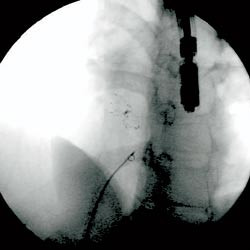

Via en 9 french (F) hylse i høyre v. femoralis, føres et kateter gjennom åpentstående foramen ovale til venstre forkammer og videre til høyre øvre lungevene. Fra denne posisjonen gjøres angiografi for å kartlegge atrienes anatomi. Deretter plasseres et ballongkateter i foramen ovale, og en måler såkalt strukket diameter, som senere brukes til å bestemme paraplystørrelse (fig 2). Ballongkateter og 9 F hylse fjernes og en lang hylse på 11 F føres til venstre forkammer. Pasienten gis heparin 7 500 IE intravenøst. En CardioSEAL paraply (Nitinol Medical Technologies, Boston, USA) (fig 3) lades i et spesielt innføringskateter, slik at de to delene folder seg sammen hver sin vei (fig 4). Paraplyen føres til venstre forkammer hvor den distale delen av paraplyen frigjøres ved at den skyves ut av innføringskateteret. Hele enheten trekkes så mot septum før man løser ut den proksimale del av paraplyen i høyre forkammer. Hele prosedyren foregår under veiledning av transøsofageal ekkokardiografi og gjennomlysning. Ved riktig posisjon står paraplyen sentralt i åpentstående foramen ovale med fire bein hvilende på hver side av atrieseptum og kan frigjøres (fig 5, 6).